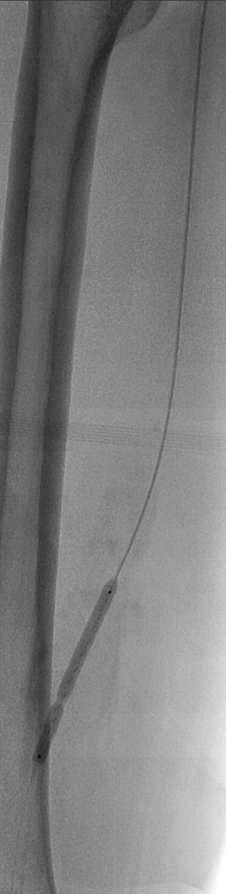

预扩:充分预扩张至关重要,需逐级使用高压球囊,最终达到 6mm 直径,以获得足够的管腔。

支架植入:遵循“由远及近”原则,先放置远端 DES,再覆盖中段 VB,最后处理近端。利用 Eluvia 的可调节性优化重叠。

后扩:常规使用 6mm 高压球囊进行后扩张,确保支架充分贴壁和管腔获得。